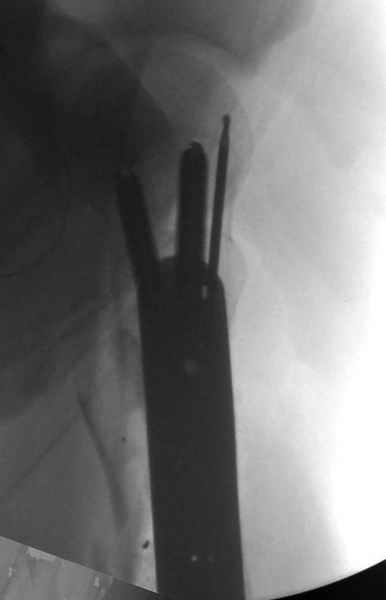

Re: [3/3] Перелом проксимального бедра

Молодой, с общим состоянием без проблем. Больной соперирован в день поступления и через два дня после операции выписан, так что не успел развиться гной.

Перелом низкоскоростным оружием, типа пистолетного, так что не стали гоняться за пулевыми фрагментами. С нервом пока подождем, иногда нерв восстанавливается если не прямое попадание в нерв, а "сотрясение" (shock wave injury).

Из всех типов фиксации взяли малоинвазивную технику мостовидной пластиной, использовали Locking проксимальную Synthes пластину.